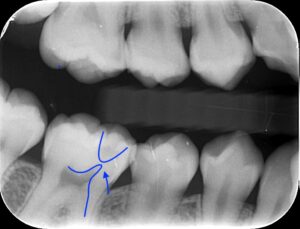

画像では下の飛び出た部分が神経で上の部分が虫歯で

非常に神経に近い虫歯となります。冷たいものや熱いものに

それほどしみず、また打診痛といって叩いても痛くない

のでMTAセメントの適応となり、MTAセメント療法を

行いました。

レントゲンではきれいにMTAセメントが埋まって

います。